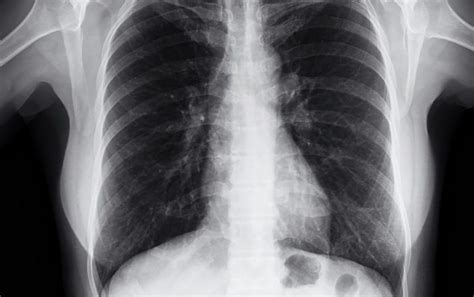

Incidental findings , also known as incidentalomas , are unexpected discoveries made during a medical imaging procedure (like a CT scan, MRI, or X-ray) that are unrelated to the primary reason for the test. Think of it this way: you go in for a scan because of a nagging cough, and the scan reveals a small, previously unknown spot on your liver. That spot is an incidental finding. It wasn’t what doctors were looking for, but it showed up anyway. These findings can range from completely harmless to potentially serious, requiring further investigation. The key is that they are unexpected and unrelated to the initial medical concern.

• Lung Nodules: These small spots in the lungs are frequently discovered on chest CT scans performed for other reasons. Most lung nodules are benign (non-cancerous), but some can be early-stage lung cancer. Further investigation, such as repeat scans or biopsies, may be needed to determine the nature of the nodule.